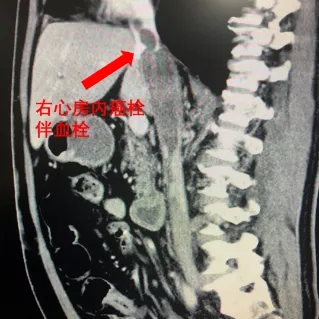

北医三院泌尿外科主任、学科带头人张树栋告诉“医学界”,患者王先生此前被诊断为肾癌伴下腔静脉癌栓,癌栓已从肾静脉侵入下腔静脉,甚至延伸至心脏附近。

患者影像资料/本文图片皆来源于北医三院

根据梅奥医学中心(Mayo Clinic)的分级标准,王先生的病情被划分为Mayo IV级,为该病的最高级别,手术风险极高。若实施手术,医疗团队将面临巨大的挑战。

张树栋介绍,患者王先生的癌栓长达15cm,其肾癌病史可能超过5年以上,情况十分严重。